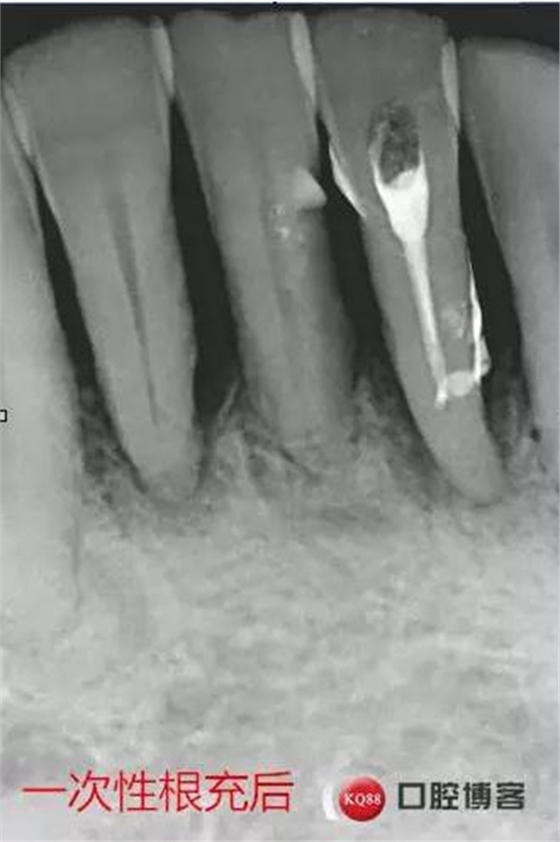

处理:上橡皮障,31开髓,测工作长度17mm,含氯冲洗液冲洗,机扩至04锥度30#,超声荡洗,一次性根充。33-43牙齿邻接处super bond粘结固位,行松牙固定。调合。拍根充术后片,未达根尖,怀疑遗漏根管,去除根充物后,继续探查根管,找到舌侧根管,测长度20mm,时间原因,未行扩根,氢氧化钙暂封。

当日根充后思考:

图省事,没有拍术中试尖片,导致术后重新去除根充物,再次探查,耽误时间。

想当然的认为31单管,忽略了尚有5-10%概率的双根管情况。

事后再次查看术前片,可以看到两个根管影像,忽略了。

处理:31去暂封,手用锉疏通根管,冲洗,机扩至04锥度30#,超声荡洗,封维塔,拍片。

处理:31去暂封,疏通根管,冲洗,试尖,拍片,根充,拍片,恰填,根尖孔外无多余药物渗出。树脂充填开髓孔。33-43树脂纤维带固定,调合抛光。